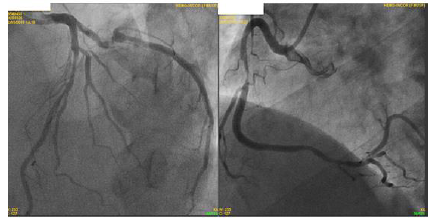

Analise as afirmativas abaixo: I. Paciente apresenta lesão grave em artéria coronária direita e a revascularização percutânea dessa lesão pode ser realizada visando melhora de sintomas. II. Paciente apresenta lesão em artéria coronária descendente anterior. O uso de métodos fisiológicos, como reserva de fluxo coronário (FFR) pode ser indicado para melhor avaliação e caso FFR menor que 0,8 a revascularização está indicado. III. Em situações de lesões triarteriais, com acometimento de coronária descendente anterior (DA) em porção proximal, há indicação de revascularização. Deve-se calcular o Synthax escore e caso ele for maior que 32, há indicação de revascularização percutânea (via hemodinâmica) e caso menor que 32, há indicação de revascularização cirúrgica. IV. Independente do tipo de revascularização a ser indicada (percutânea ou cirúrgica), o paciente deve receber dupla antiagregação plaquetária por 1 ano, com indicação Classe IA de diretrizes.